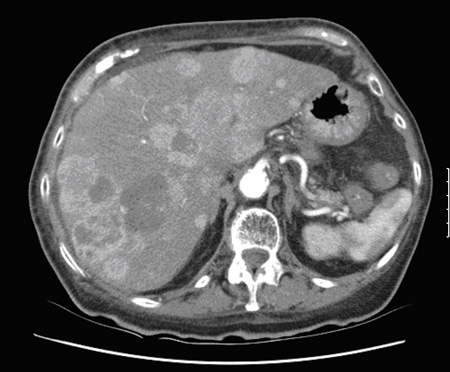

Tomografia computadorizada (TC) mostrando múltiplas metástases hepáticas

Do acervo de Dr. R. Srirajaskanthan e Dr. M. Caplin; usado com permissão